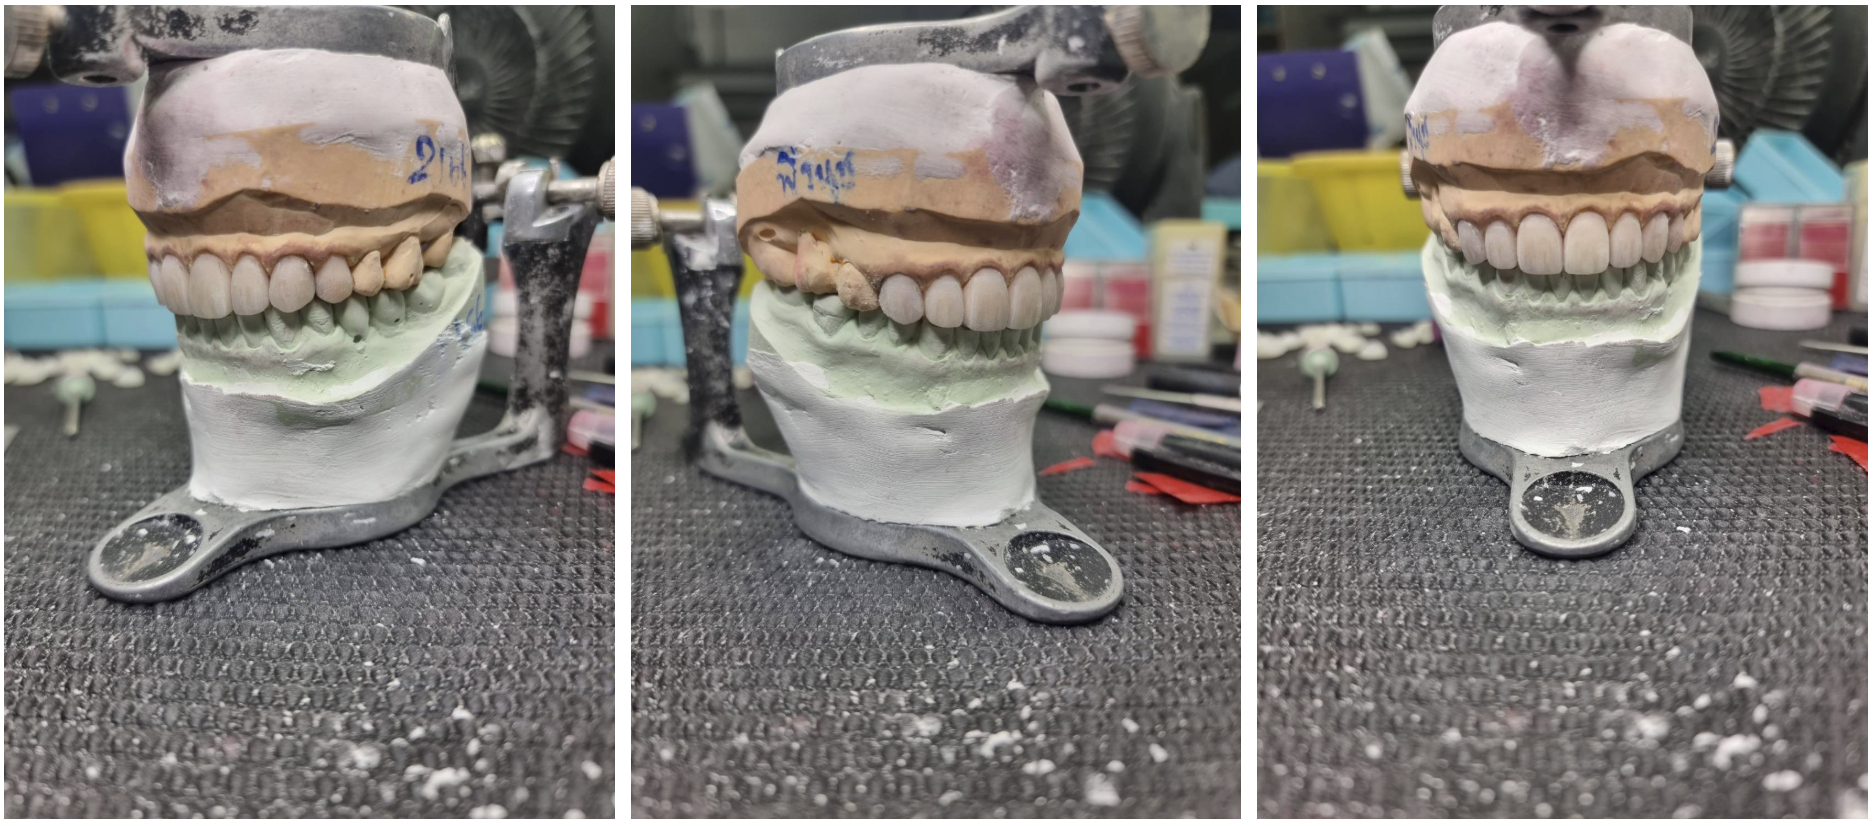

1. Direct Mock-up (Try Your Smile First)

Before starting treatment, a temporary mock-up is placed directly on your teeth—allowing you to see and feel your new smile in real life. You can evaluate the shape, length, and proportions immediately, and request adjustments before any permanent procedure begins.

One of the most valuable aspects of Signature Smile Design is the ability to preview your new smile before committing to treatment. With a direct mock-up, patients can experience how their smile looks and feels in real life—making the decision process more confident and informed. Since smile transformation often relates to first impressions and personal confidence, being able to “try before you begin” ensures that the final result truly reflects your expectations. This step is especially helpful for patients who want reassurance before investing in a full smile makeover.